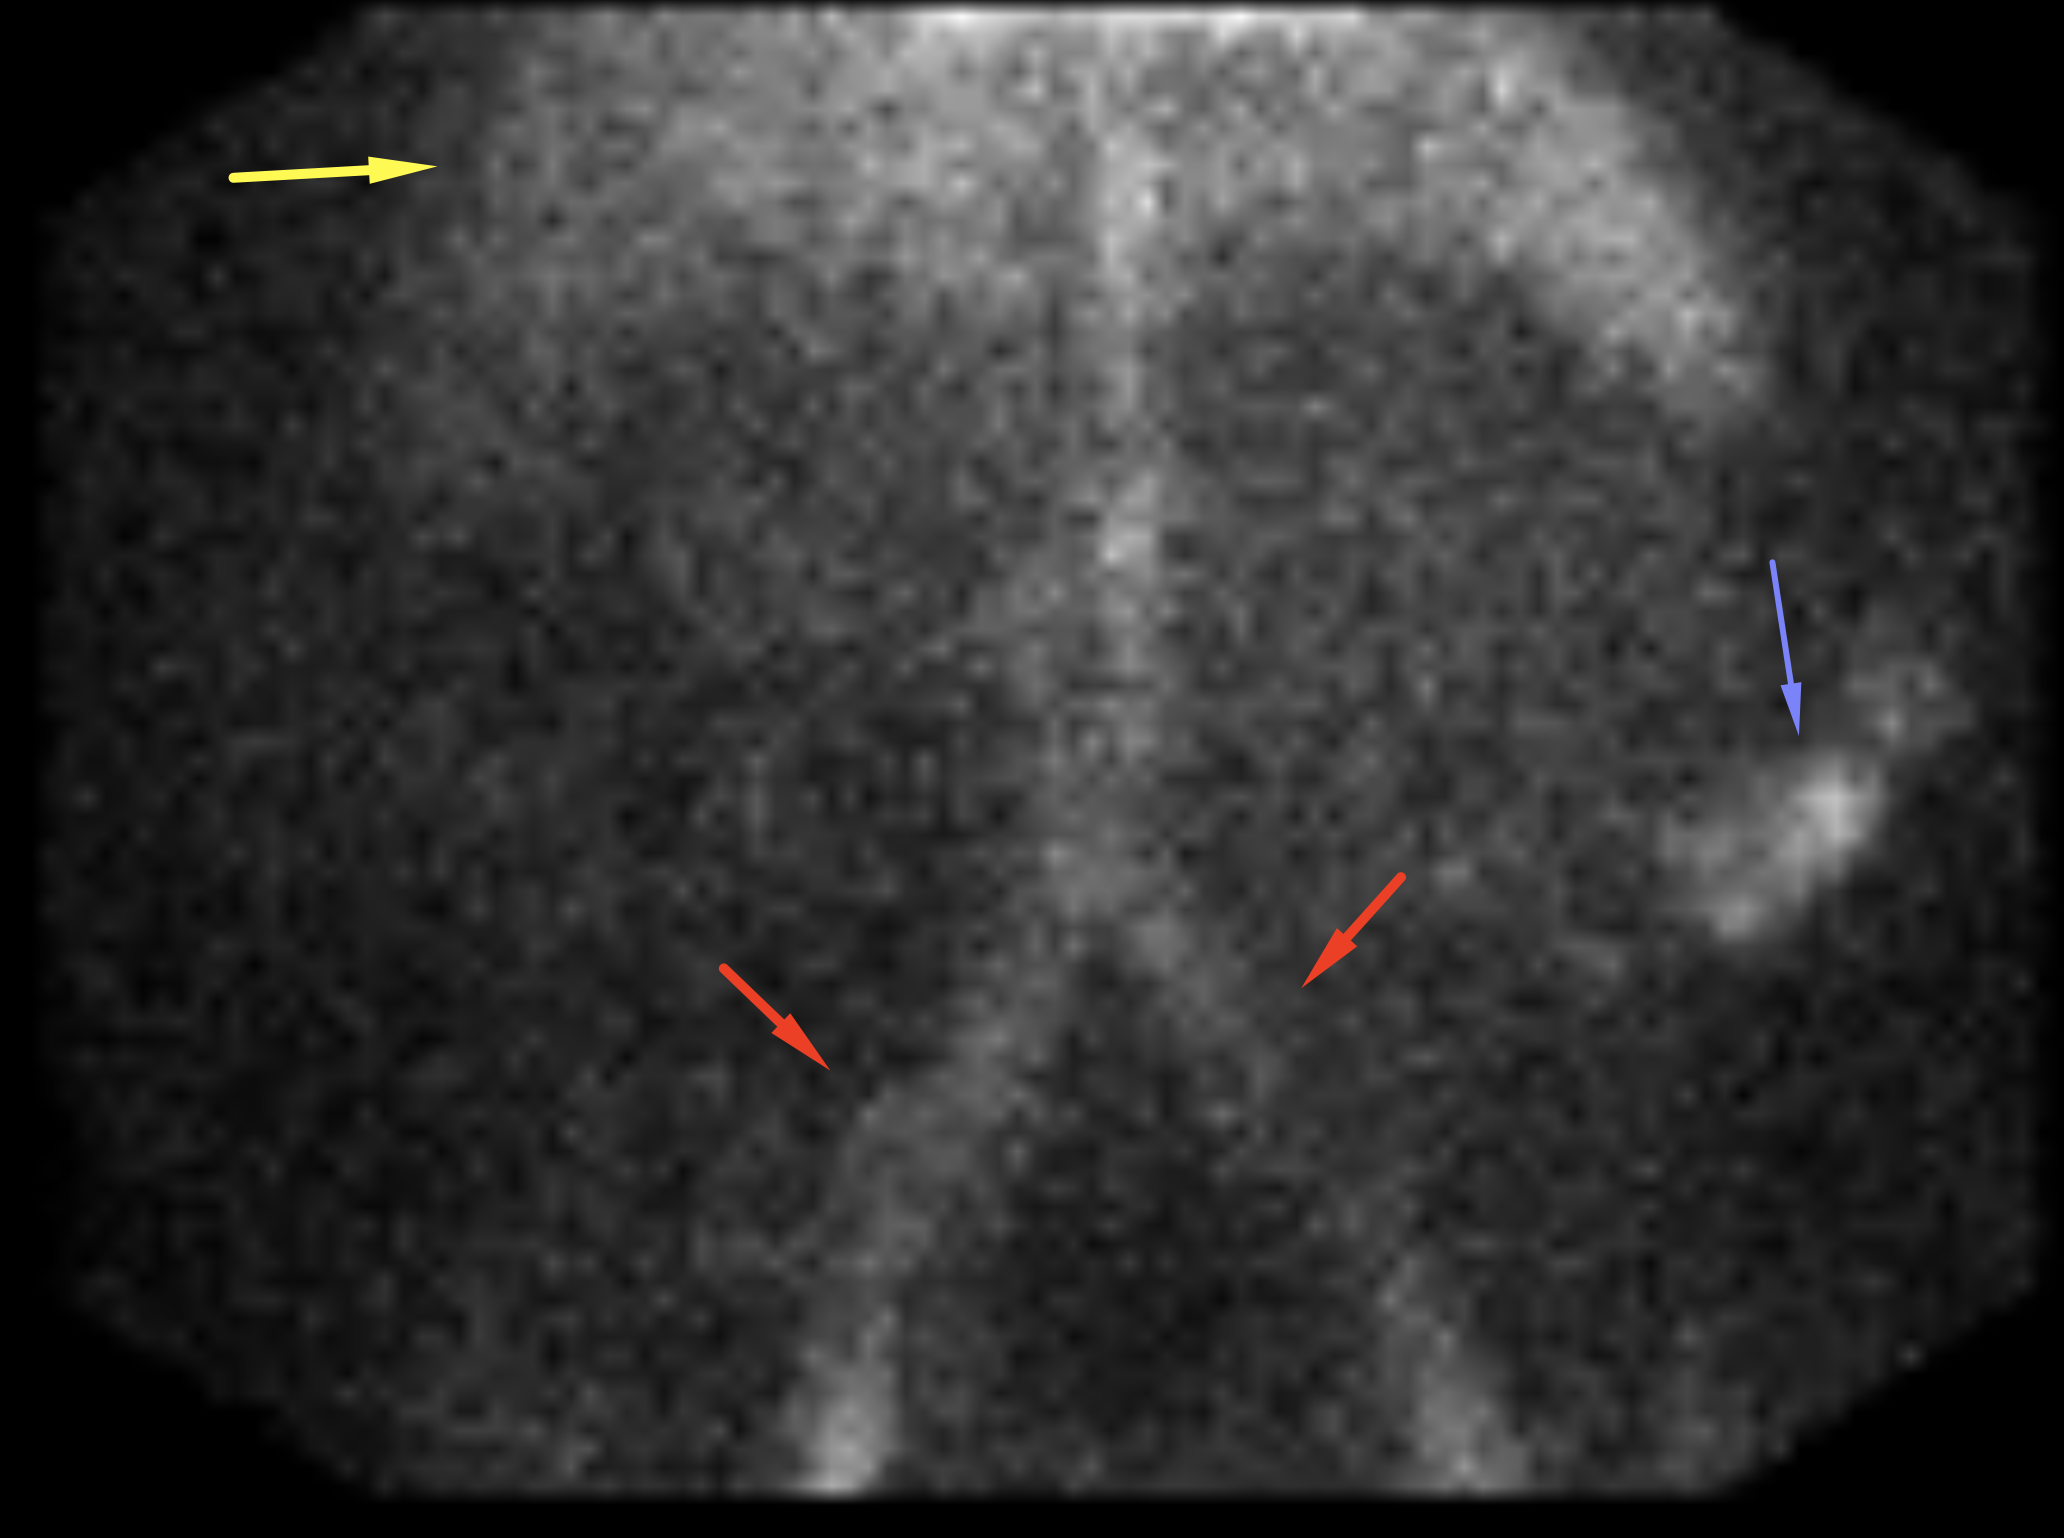

Age: 72

Sex: Male

Indication: Hematochezia and hypotension

Radiotracer: Tc99m labeled RBCs

Sample ReportPositive for active GI bleed, likely originating in the descending colon.